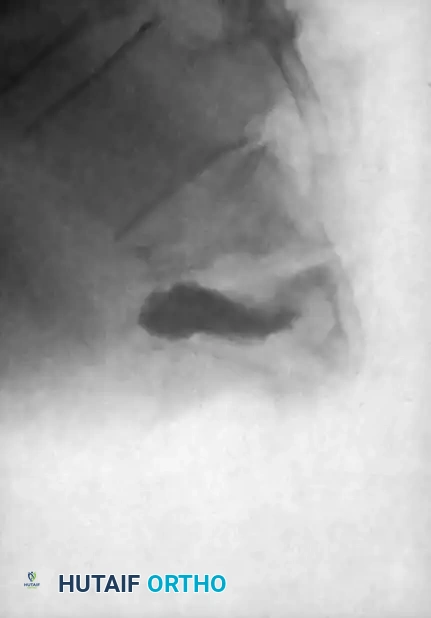

Associated Surgical & Radiographic Imaging